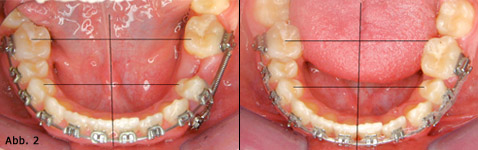

Minischrauben haben viele Vorteile, von denen stellvertretend hier nur zwei genannt seien. In vielen Fällen kann die Behandlung mit wenig Aufwand und als „invisible alignment“ durchgeführt werden. Nebenwirkungen, wie sie bei minimaler oder mittlerer Verankerung zwangsläufig auftreten, sind nahezu ausgeschlossen (Abb. 2).

Abb. 2 Einseitiger Lückenschluss im 3. Quadranten. Die Minischraube verhinderte die Verschiebung der Mittellinie als eine sonst häufig zu erwartende reaktive Nebenwirkung.